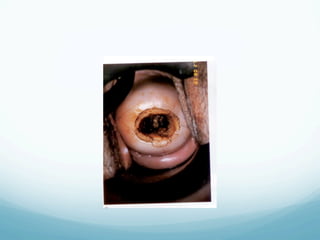

Cryotherapy

—  Office procedure using local anesthesia and

NSAID s

—  Using refrigerant gas (CO2 or N2O)

—  The ectocervix must be cooled to -20 C to cause

crystallization of intracellular water and destroy the

lesion

—  It is achieved by forming an ice ball in the cervical

tissue that is at least 5 mm from the tip of the

probe

Cryotherapy —  Office procedureusing local anesthesia and NSAID s —  Using refrigerant gas (CO2 or N2O) —  The ectocervix must be cooled to -20 C to cause crystallization of intracellular water and destroy the lesion —  It is achieved by forming an ice ball in the cervical tissue that is at least 5 mm from the tip of the probe